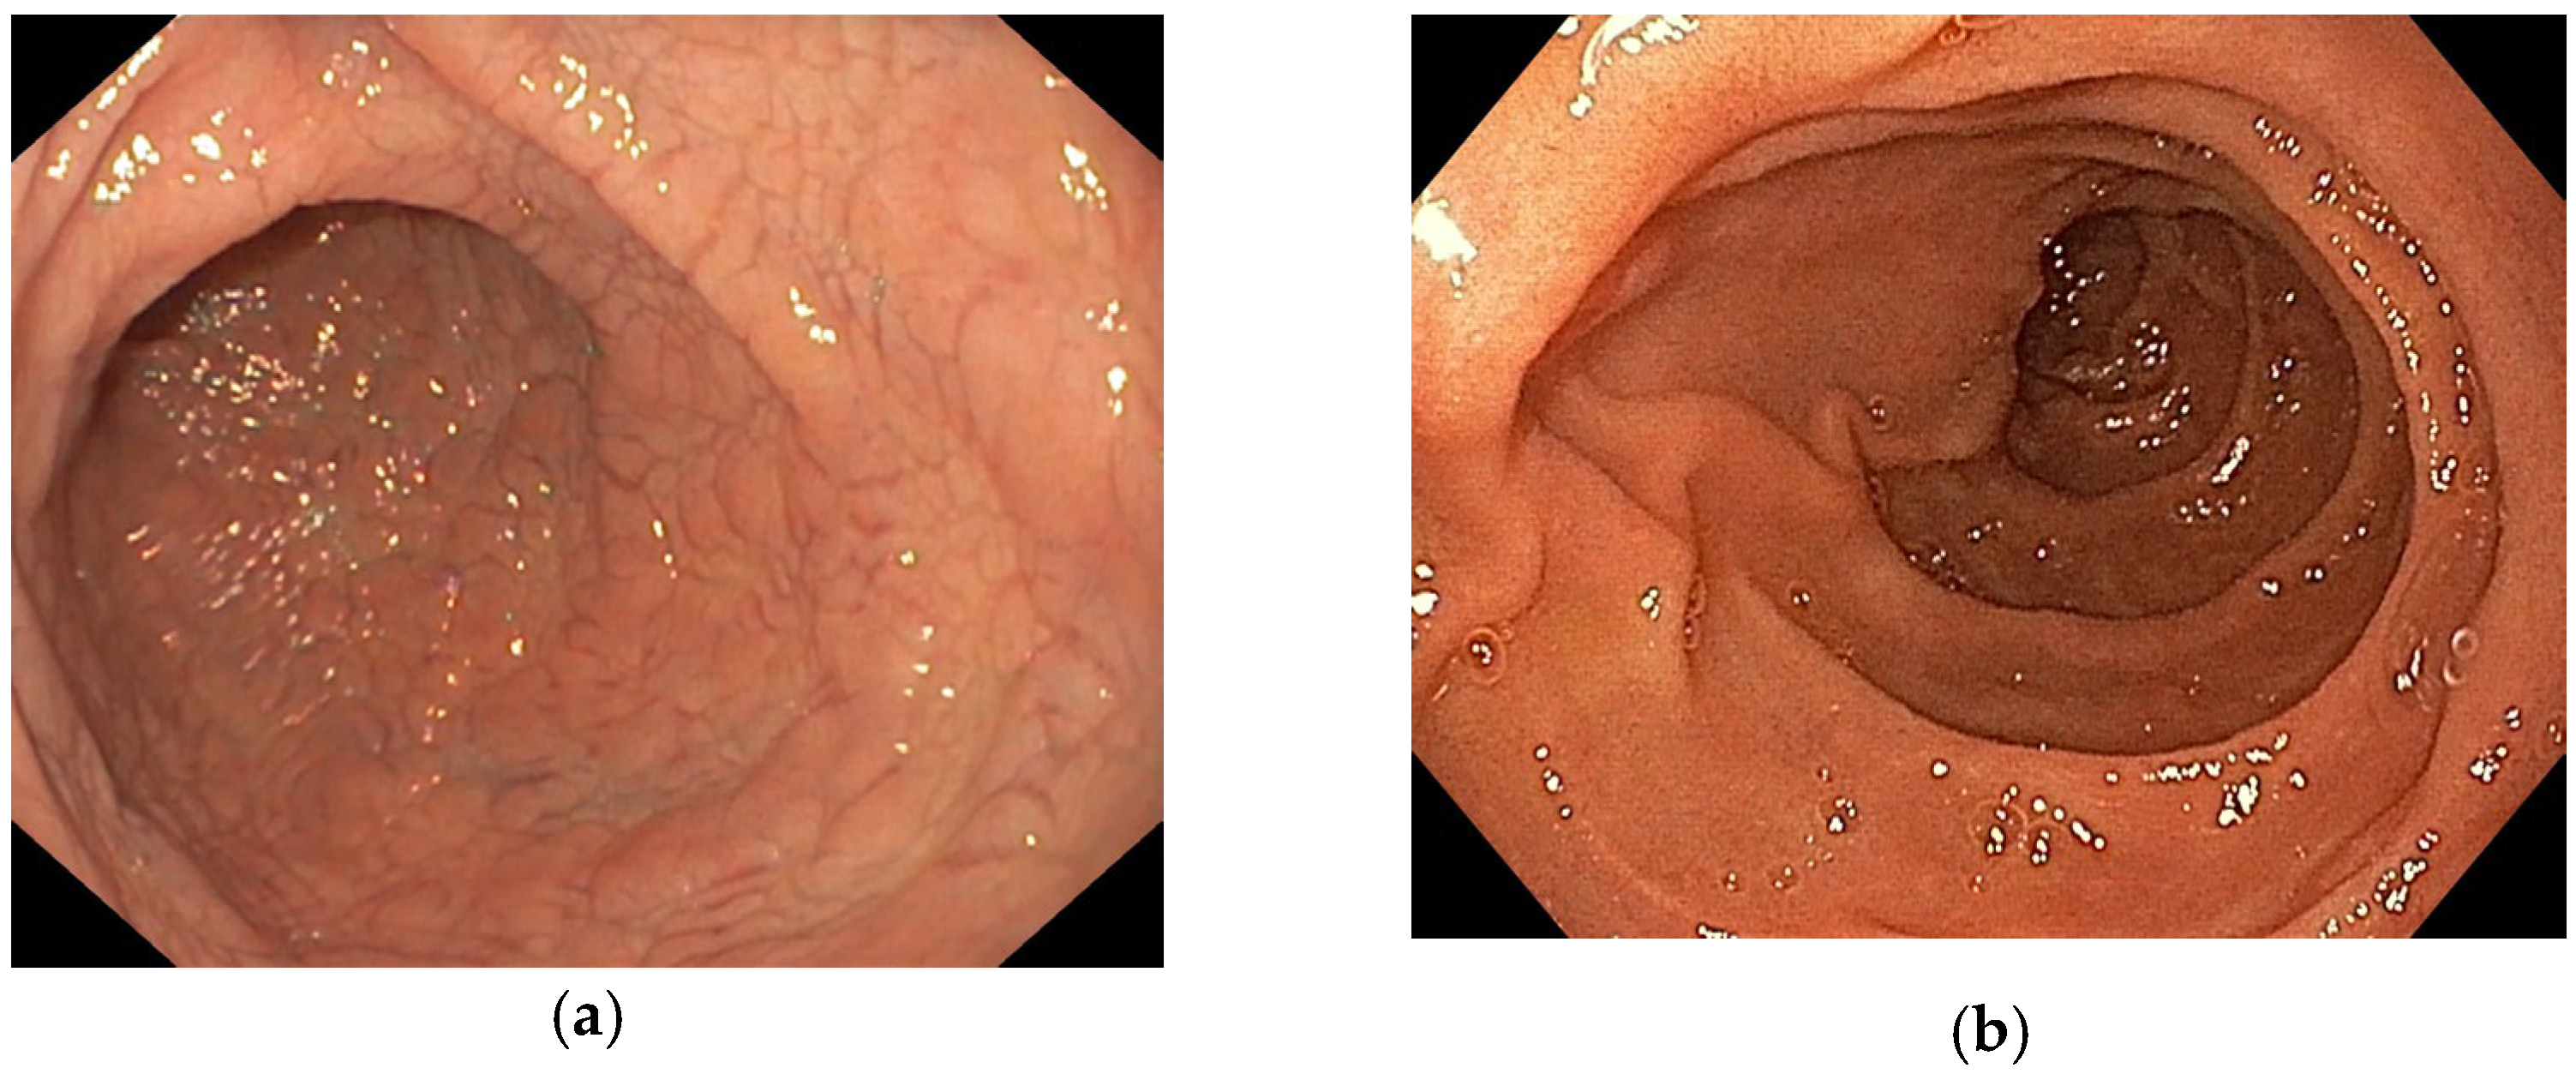

| Atrophy of mucosa with prominent submucosal vascular pattern; Mucosal fissures or grooves, with mosaic or “cracked-mud” appearance; Nodularity of the mucosa; Scalloping of Kerckring folds; Reduction or loss of folds. |